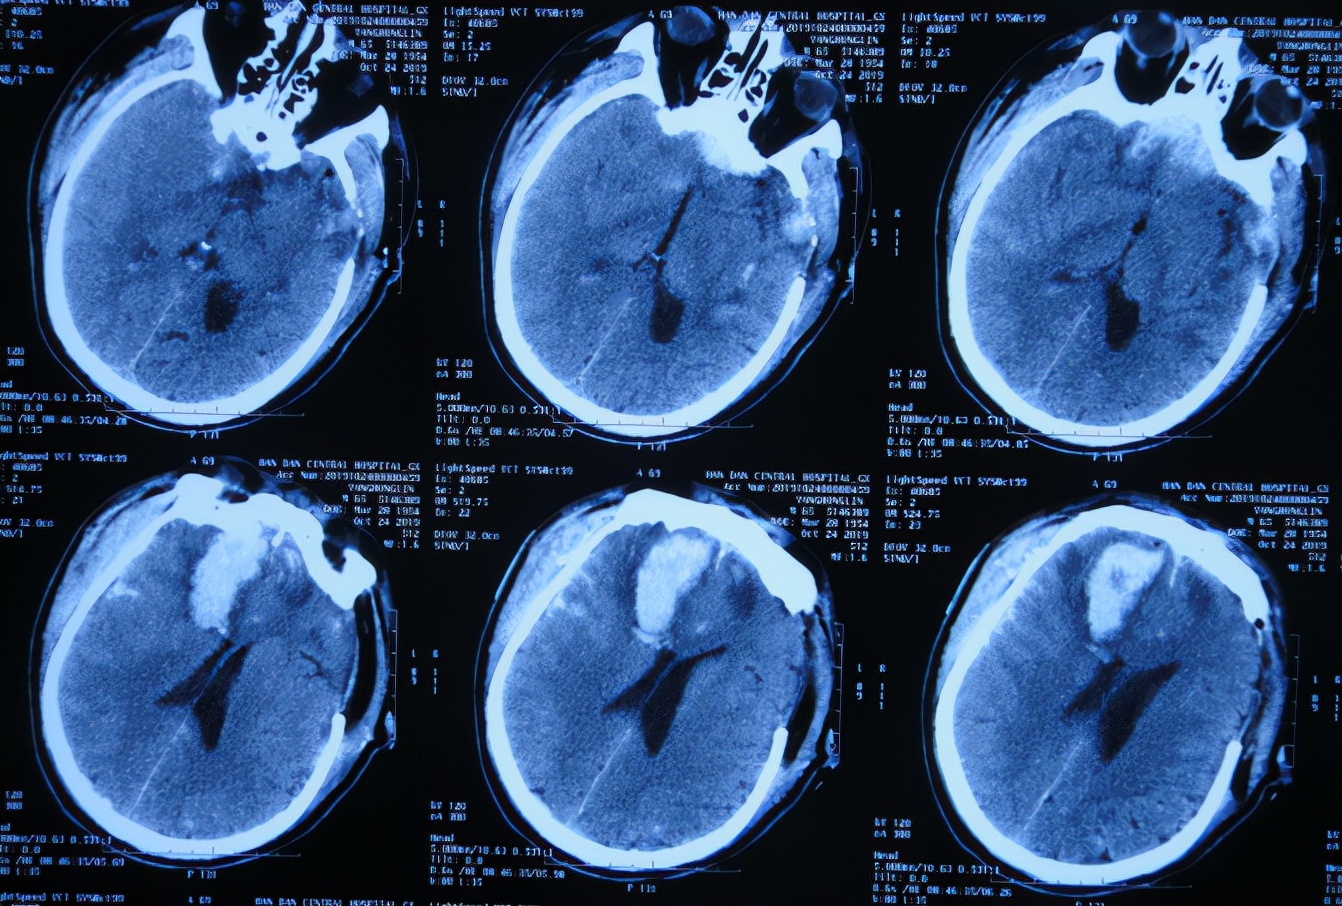

颅骨修补术后33天即第1次脑室分流管拔除后27天2020年1月15日,进行了第2次的脑室腹腔分流术( 图-22 )。

图-22: 2020年1月15日头颅CT

颅骨修补术后35天即第2次脑室腹腔分流术后2天2020年1月17日,病情稳定,查头颅CT( 图-23 )后认为无异常。

图-23: 2020年1月17日头颅CT

颅骨修补术后40天即第2次脑室腹腔分流术后7天即2020年1月22日(第2家医院住院治疗43天)出院,转住入第3家的北京某康复医院进行康复治疗。